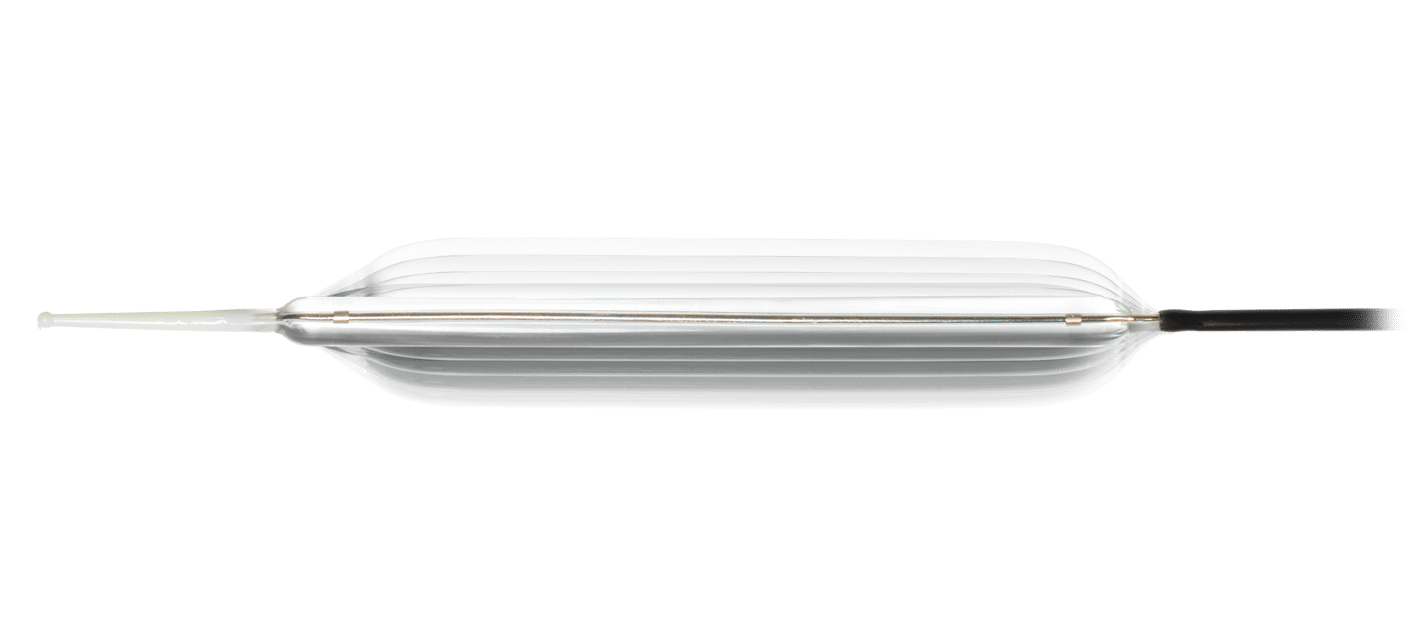

HEART ATTACK

A heart attack, also known as a myocardial infarction, occurs when heart muscle doesn’t receive enough blood. As time passes without receiving treatment, the more damage is done to the heart. The main cause of a heart attack is coronary artery disease (CAD). Researchers have found that throughout life, men are about twice as likely as women to have a heart attack.

Learn more about heart attacks. Explore our Cardiac Portfolio, including our radial sheaths, catheters, wires, and compression devices.

MERIT PRODUCTS